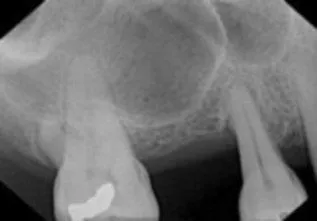

Implant placement with using Sinus Bone Graft

Before